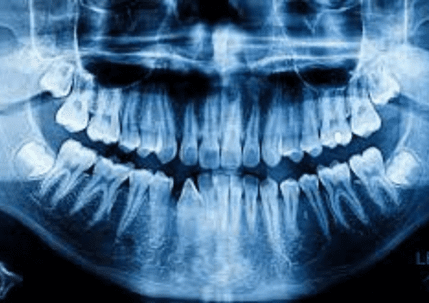

The risk of getting dental decay is not something that should be taken lightly. Cavities can appear unexpectedly, create a severe toothache, and essentially put your life on halt until they are treated. What is tooth decay, and what causes it? The food particles that remain in your mouth after you eat turn into plaque. Acid is produced when the bacteria in plaque break down the sugars and carbohydrates that are present in your mouth. This acid is powerful enough to soften and destroy the enamel, which is the outer coating of a tooth. This condition is known as dental decay, or a cavity. Stages, Symptoms, and Treatments of Tooth Decay

Because tooth decay has numerous stages, there are a variety of symptoms that you may see, feel, or even taste at times. The treatment you will require for your cavity will be determined by how serious the decay is and where it is located. Stage 1: The enamel is decaying. A cavity has not yet passed through the enamel, which is the outer coating of the tooth, during its early stages. During this period, symptoms are not very severe. In fact, you might not notice any of them at all. Sometimes, you may notice that your tooth has darkened, or you may feel a little sensitivity. Our Summerlin dentist will remove the area that has enamel decay and fill the empty space with a tooth-colored filling material in order to repair the decay. Fillings are a quick and inexpensive option that can last for many years. Stage 2: Dentin After the decay has passed through the enamel surface, it will reach the dentin layer. The dentin layer is fragile and is particularly susceptible to decay. This means that if the cavity reaches the dentin, it can spread quickly. During this stage, you will notice that your tooth sensitivity is more pronounced. You might feel uncomfortable when you eat sweets, clean your teeth, or are in chilly conditions. If the decay has impacted much of your tooth, our dentist in Summerlin may suggest that you get a crown instead of a filling. A crown is a hard cap that goes over your tooth and protects it from further harm. Because this treatment is more complex, it does take longer to finish. Additionally, it is more expensive than simply a basic filling. However, if crowns are manufactured and maintained correctly, they can last for many years, making your investment worthwhile. Stage 3: Pulp Chamber The decay will enter the pulp chamber once it has passed through the dentin layer. This is the section of the tooth that has blood arteries, nerves, and connective tissue. Your tooth will become infected after the cavity has reached the pulp. You will go through a lot of discomfort during this time. You may also start to feel uncomfortable due to heat, in addition to chilly weather. You may also experience persistent discomfort that necessitates the use of pain medication to alleviate it. We will take an x-ray of your tooth to make sure that the cavity has reached the pulp chamber. Root canal therapy will be necessary to fix and protect your tooth. This surgery consists of taking out the nerve tissue, cleaning the canals, and closing them off in order to stop bacteria from coming back in. You will probably need to be fitted for a crown in addition to receiving therapy on the nerves of your tooth. This will help to prevent additional harm to the tooth that is already at risk. Stage 4: Abscess The roots of your teeth are the parts that you cannot see when you look inside your mouth. They are located in the jaw. Nerve channels that go down each root extend beyond the pulp chamber. If your cavity has reached the nerves in the root of your tooth, you may have a terrible pain and swelling in your face. If you have an abscess, you will see a little bump on your gums, which is called a fistula. A dental abscess is a major medical issue. You might not find any relief from over-the-counter pain drugs. The toothache could prevent you from sleeping at night or cause you to wake up often. The gum tissue surrounding the tooth that is impacted may swell, and this swelling could migrate to your face. You might possibly develop a fever. If a cavity has caused a serious infection, it may not be possible to salvage the tooth with a root canal. It may be essential to do an extraction. We will be able to determine the state of your tooth and if it can be saved by using a dental x-ray. If it turns out that we need to take it out, a dental implant or a bridge could be a good option for you to replace it. Preventing Cavities Maintaining excellent dental hygiene is the most effective approach to avoid cavities. Make sure to have frequent cleanings and check-ups with your dentist in Las Vegas so that any problems can be addressed as soon as they arise. If you haven't gone to the dentist in a while or think you might have a cavity, you should make an appointment with Dr. Cohan at Summerlin Dental Solutions. Make an appointment by calling or book online today. GET TO KNOW YOUR BEST DENTIST IN SUMMERLIN